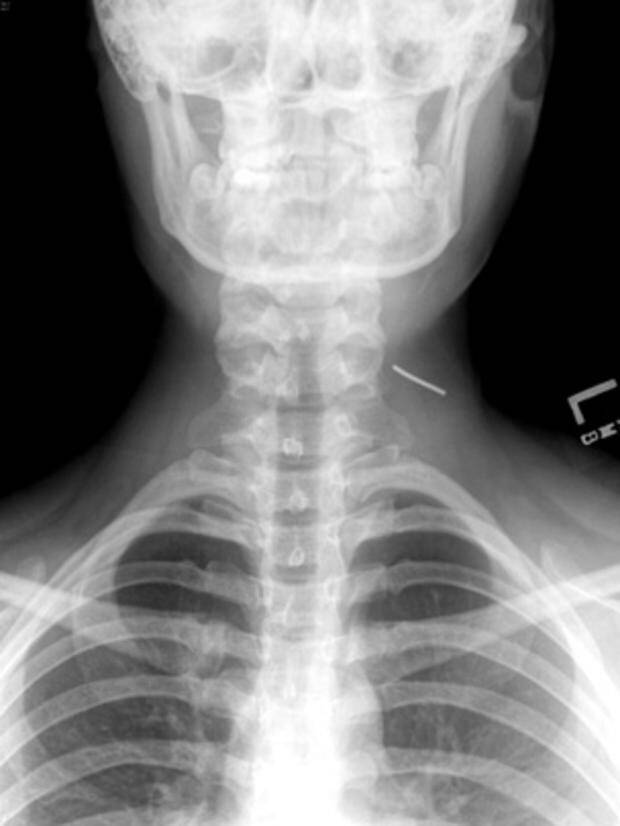

Niektórym osobom, zwłaszcza w wieku nastoletnim, trudno jest się powstrzymać od umieszczania rzeczy pod swoją skórą. Lekarze twierdzą, że rośnie liczba nastolatków – zwłaszcza z depresją lub lękami – które wbijają igły, zszywki, spinacze oraz inne przedmioty pod skórę swojego ciała. Tę dość bezkrwawą praktykę lekarze nazywają czasem “zachowaniem samo-osadzającym” lub “zagnieżdżającym”.

Samookaleczenia są niebezpieczne – oprócz ryzyka wywołania infekcji, umieszczanie w ciele przedmiotów może uszkodzić nerwy lub naczynia krwionośne. – W skrajnych przypadkach oprócz krwawienia (w tym wewnętrznego) może wystąpić nawet udar – powiedział Shiels.

– Jeśli dasz niektórym z tych dzieciaków magazyn do poczytania, to odzyskasz go z brakującymi zszywkami – mówi Shils. – Daj im ołówek, a wyciągną grafit i wsadzą do pod skórę.